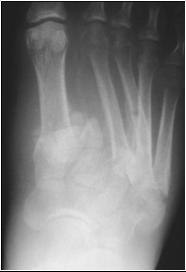

May be subtle

May be obvious